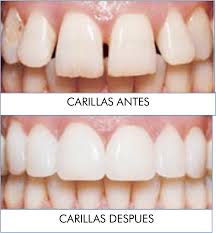

Carillas estéticas

Es un tratamiento altamente estético que devuelve la funcionalidad y la estética a tus dientes, por manchas tabaco alcohol, pequeñas roturas o fisuras desgastes etc.

Es un tratamiento que no requiere anestesia, rápido y es totalmente indoloro.